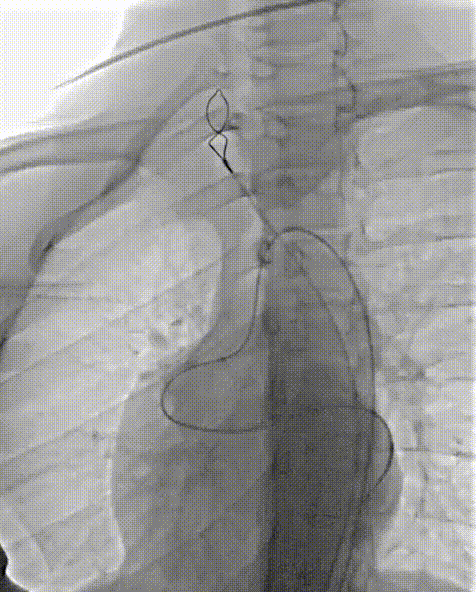

送入14mmAVP-II血管封堵器并定位释放

造影检查封堵位置及封堵效果